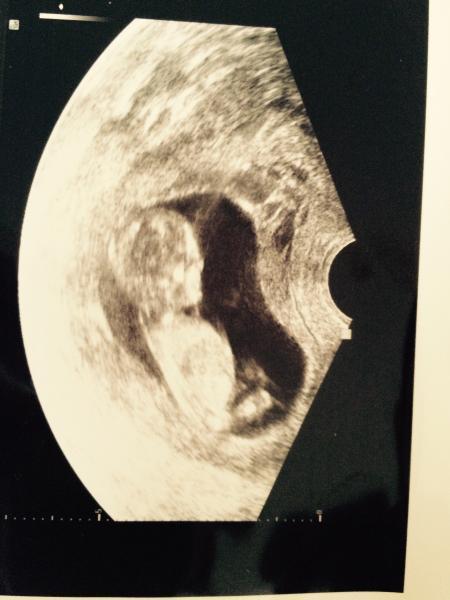

Hatte heute endlich meinen nächsten Termin und es war unglaublich schön die ganzen Sorgen umsonst :-)

Mein Baby hat kräftig gezappelt und sonst auch alles super

Hab euch noch ein wunderschönes Bild im Anhang

So ein schönes Bild! Ach ja ich freue mich schon auf Freitag xD da darf ich dann auch wieder Krümmel schauen! Mal sehen was mein kleiner Bauchakrobat sich diesmal ausdenkt um die FA zu ärgern xD beim letzten Mal hat sie dauernd vor sich hingemurmelt das doch endlich mal Ruhe ist damit Mama ein schönes Bild mit nach Hause nehmen kann! Hat leider nicht so geklappt ^^ aber das bin ich ja schon von meiner letzten Ss gewöhnt . Schön das alles i.O.ist ^^ LG Lilly